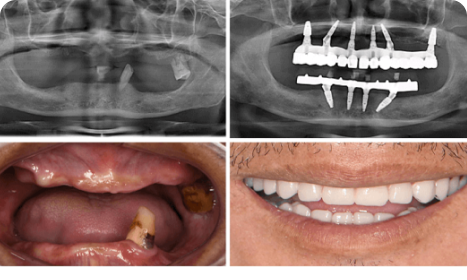

What are Full Mouth Dental Implants?

Full Mouth Dental Implants are beneficial for those who have lost a majority if not all of their teeth or have severe dental issues. The process consists of multiple implants placed in the jawbone and on each of the implants, a full set of prosthetic teeth is affixed. It provides unmatched functional strength, natural appearance, and great reliability for years—allowing patients to eat, talk, and smile confidently as if they had natural teeth.

Are You the Right Candidate for Full Mouth Dental Implants?

You’re likely suitable if you:

👉Have missing teeth or severely damaged teeth.

👉Have enough healthy jawbone or are eligible for zygomatic implants.

👉Are committed to maintaining good oral hygiene post-procedure.

Our specialists will evaluate you thoroughly to guide the best option.